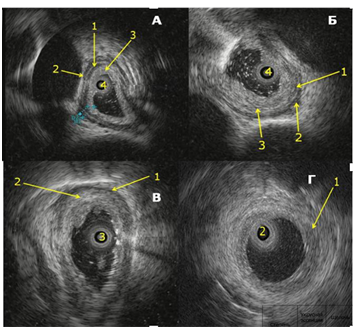

Digital Formats: During EUS, damaged esophageal wall layers were highly echogenic with a heterogeneous echo structure. Increased thickness and impaired differentiation of the contours and boundaries of the damaged esophageal wall layers were noted. Based on changes in their structure during EUS, we developed the following grading for damage to the muscular layers of the esophageal wall: grade 4a, 4b, 4c, 4d (Fig. 1 and Fig. 2).

Fig 2. A – Grade 4a esophageal reflux disease. 1 – Impaired differentiation of the mucosa and submucosal layers, 2 and 3 – thickened circular and longitudinal muscle layers, 4 – ultrasound mini-transducer.

B – Grade 4b esophageal reflux disease. 1 – Partially damaged circular muscle layer, 2 – intact longitudinal muscle layer, 3 – damage extending to the submucosal and circular muscle layers, 4 – ultrasound mini-transducer.

B – Grade 4c esophageal reflux disease. 1 – Partially damaged longitudinal muscle layer, 2 – damage extending to the submucosal, circular muscle, and partially longitudinal muscle layers, 3 – ultrasound mini-transducer.

D – Grade 4d esophageal reflux disease. 1 – damage extending to all layers of the esophageal wall, 2 – ultrasound mini-transducer.